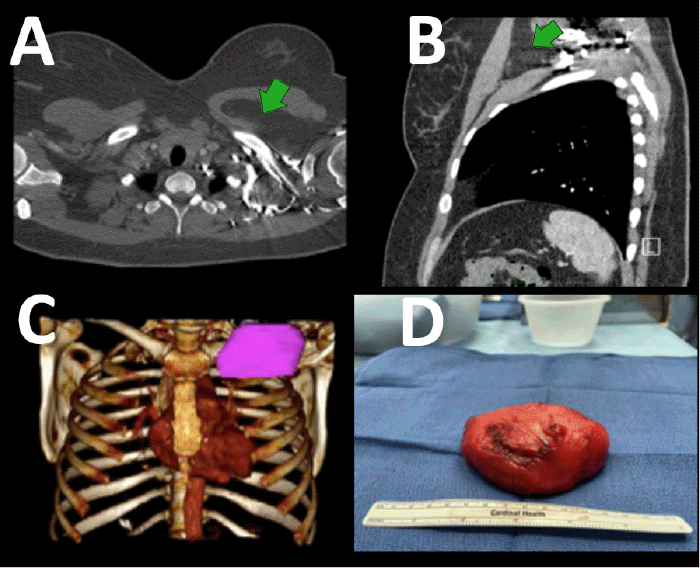

The third case is of a 40-year-old female who originally presented to the emergency room with chest pain. A CT scan discovered a left chest wall intramuscular mass, sandwiched between the pectoralis major and minor. Radiographic features were consistent with lipoma. At that time, it measured 8.1 × 5.0 × 3.6 cm. She did not present to the thoracic surgery clinic for another year and a half, at which time her chest wall pain had worsened, and the mass now measured 9.4 × 4.6 × 5.7 cm (Figure 3). She underwent resection via an incision lateral to her pectoralis major muscle. The muscle was lifted, and the mass bluntly separated off the pectoralis major and minor muscles. Blind palpation was utilized for the majority of the dissection. A drain was placed in the space, and she was discharged on POD 1. Operative time was 76 minutes. The final measurements were 9.2 × 6.7 × 4.6 cm.

Figure 3. A) Axial CT Scan (green arrow denotes mass), B) Sagittal CT Scan (green arrow denotes mass), C) 3D Reconstruction (mass in purple, airway in blue), and D) Resected Lipoma. Published with Permission